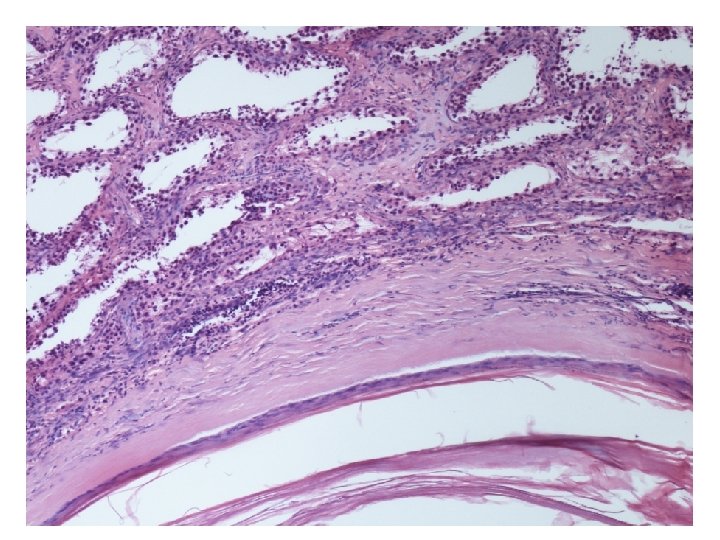

Mikroskopické vyšetření • tkáň varlete se stěnou cysty tvořenou různě silným hyalinizovaným vazivem s různě intenzivní kulatobuněčnou zánětlivou celulizací, která je ložiskově vystlaná zachovalým rohovějícím vrstevnatým dlaždicovým epitelem • v lumen cystického útvaru keratinové hmoty • v okolí cystického útvaru atrofické a hyalinizované semenotvorné kanálky

• případ byl pro podezření na ložiskovou přítomnost GCNIS zaslán ke konzultaci do Bioptické laboratoře Plzeň • screeningový marker GCNIS OCT 3/4 byl kompletně negativní • GCNIS nebyla prokázána

teratom prepubertálního typu (nezávislý na intratubulární germinální neoplázii), tzv. epidermální cysta